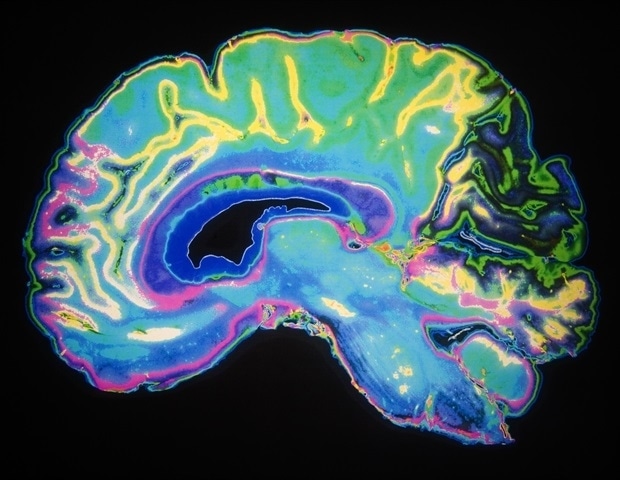

Исследователи из Университета Макгилла определили функцию мозга, которая помогает объяснить, почему детский стресс повышает метаболические риски для здоровья у некоторых женщин в более позднем возрасте.

Новое исследование показало, что изменения в сети инсулиновых рецепторов мозга влияют на то, как женщины реагируют на невзгоды в раннем возрасте. Этот эффект оказывает меньшее влияние у мужчин, что позволяет предположить, что здесь задействован процесс, специфичный для пола.

Результаты, опубликованные в Communications Biology (Nature Portfolio), указывают на то, что сеть рецепторов инсулина в мозге является многообещающим средством раннего выявления и будущих стратегий профилактики метаболического синдрома, основной причины сердечно-сосудистых заболеваний, от которых страдает примерно каждый пятый взрослый канадец.

Анализируя данные более чем 32 000 взрослых, исследователи обнаружили, что среди женщин, которые рано пережили неблагоприятные условия, только у тех, у кого был определенный образец инсулиновой функции мозга, наблюдалось увеличение брюшного жира и более высокий риск метаболического синдрома.

У каждого человека есть функция мозгового инсулина, которая варьируется от человека к человеку и, по-видимому, является встроенной особенностью мозга, а не чем-то, сформированным стрессом, отмечают исследователи.

Инсулин, хорошо известный тем, что регулирует уровень сахара в крови, также играет важную роль. играет важную роль в познании и поведении. Поскольку инсулин нелегко измерить непосредственно в мозге, исследователи разработали метод, который использует ДНК для определения оценки.